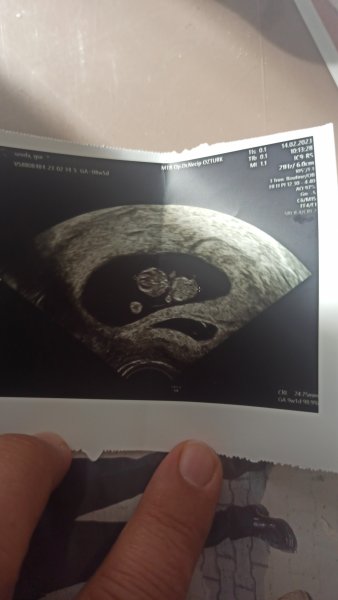

Aslında gerçekten insan çok heyecanlaniyor ilk gebeliğim arkadasim geçen hafta bır guruba yazmış bende merak ettim tabi yinede en iyisini Allah bilir fakat yine insanı tatlı bir merak sarıyor teşekkür ederim şimdiden canım.